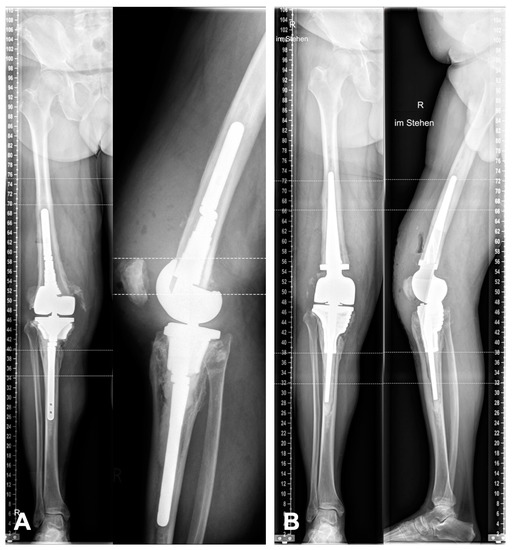

2.4. Planning and Surgical Technique

3. Results